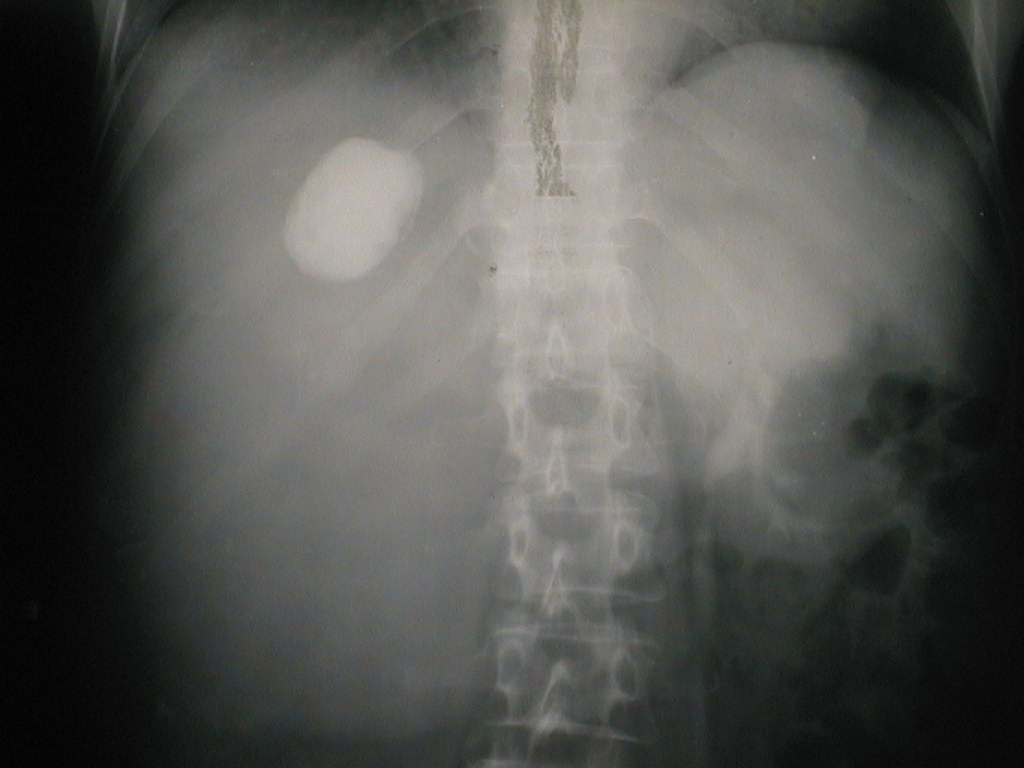

Urography: normal left kidney, surgical absence of right kidney.Right upper quadrant intense opacity suggests a calcificated hydatid cyst.

Urografie: rinichiul stâng funcțional, rinichiul drept absent chirurgical. Jumătatea dreaptă a abdomenului ocupată de o imagine opacă. Opacitatea  intensă din hipocondrul drept corespunde unui chist hidatic calcificat.

Computed Tomography: radioopaque retroperitoneal mass, placed in the right abdominal half; surgical absence of right kidney.

Tomografie computerizată: formațiune moderat radioopacă ocupând spațiul retroperitoneal în jumătatea dreaptă a abdomenului (+). Rinichiul drept absent chirurgical.